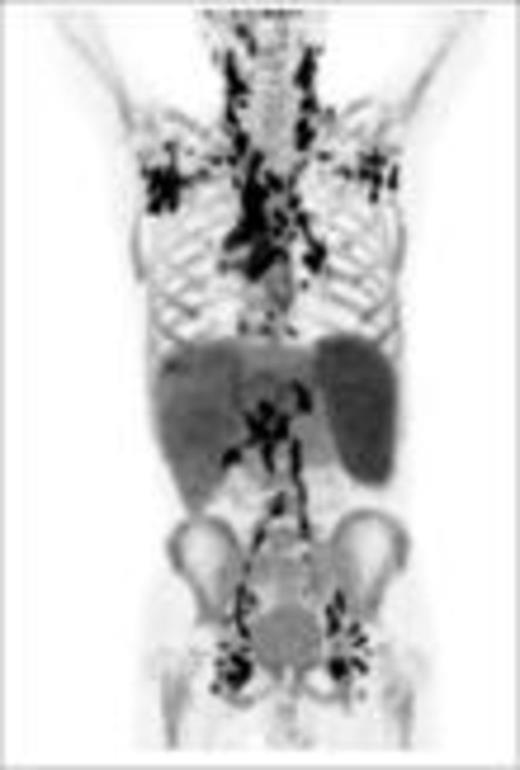

Baseline (pt#1) after 1 x PREBEN (pt#1)